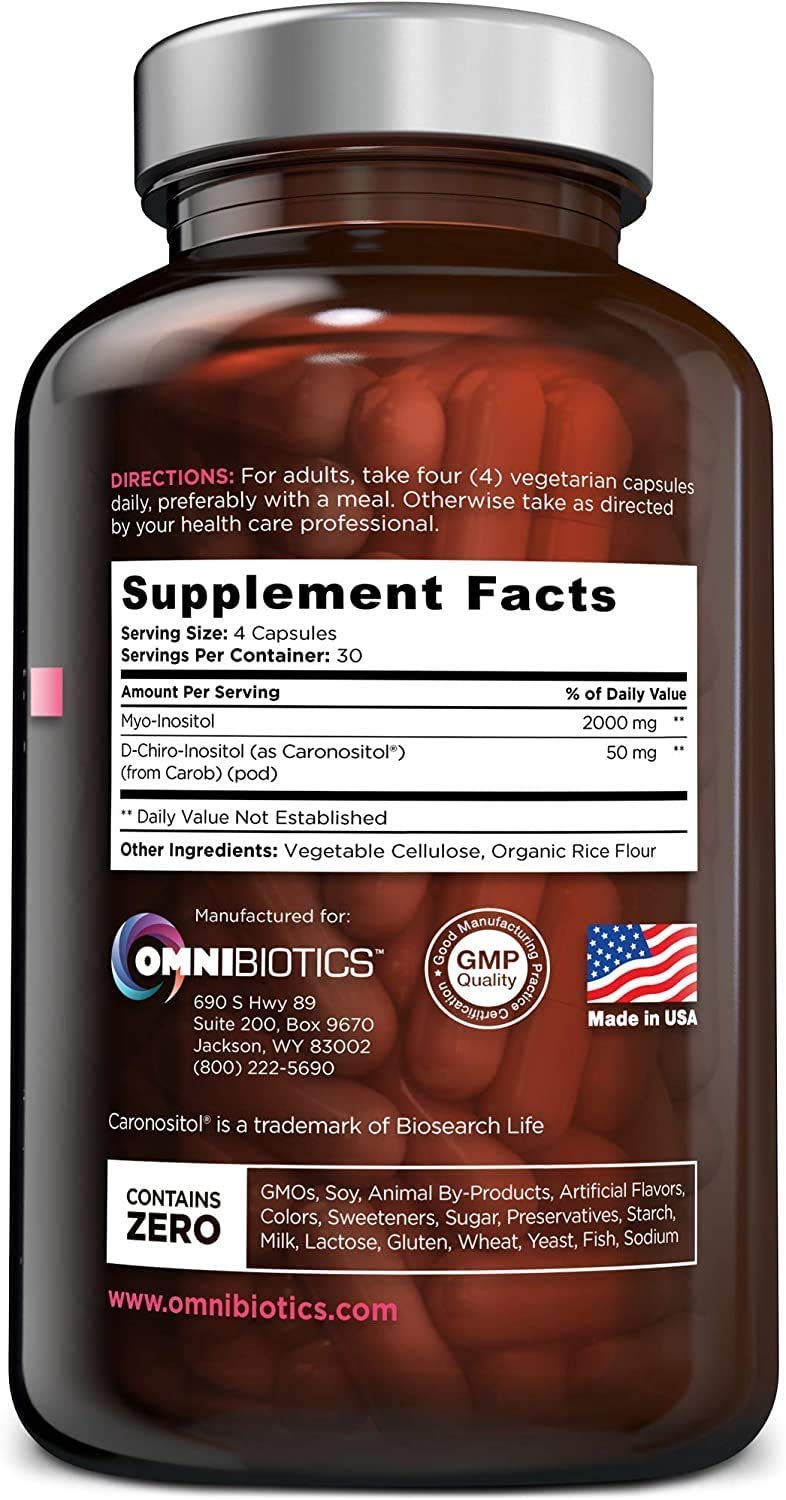

Myo-Inositol Plus & D-Chiro-Inositol | PCOS Supplement | Helps Promote Hormone Balance and Support Ovarian Function | Natural Fertility Supplements (120 Capsules)

OmniBiotics Myo-Inositol Plus with Caronositol features myo-inositol and

d-chiro-inositol at 2,000 mg and 50 mg each respectively, per serving. Myo-

Inositol Plus is a safe and effective myo inositol with d chiro supplement

option. 120 veggie caps 30 day supply These statements have not been

evaluated by the FDA. This product is not intended to diagnose, treat, cure,

or prevent any disease. Caronositol is natural D-chiro-inositol botanical

extract (minimum 95%) purified from carob pod by a solvent-free patented

process. ‣ Made In the USA within a FDA inspected, NSF and cGMP certified

facility ‣ 100% vegetarian / vegan friendly, Non-GMO ‣ Contains no gluten,

wheat, dairy soy, yeast, animal products, artificial colors, or artificial

preservatives

- 100% NATURAL, NON-GMO, NO BINDERS or ADDITIVES Our clinical-strength, Myo-Inositol Plus supplement is 100% free of: gluten, soy, nuts, dairy, sugar, animal by-products, artificial ingredients, chemicals, preservatives and fillers. We also do testing at every stage of the manufacturing process to ensure all ingredients are free of heavy metals. Made in the USA in a NSF-certified, FDA-registered, cGMP facility.

- Brand: OmniBiotics

- Flavor: Unflavored

- Primary Supplement Type: Myo-Inositol

- Unit Count: 120.00 Count

- Item Form: Capsule